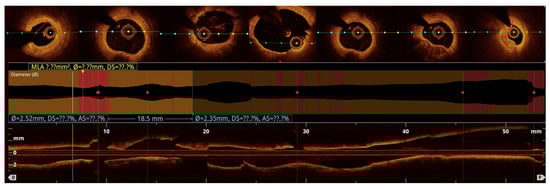

OCT-based analysis of aneurysmal remodeling:

Quantitative analysis was performed using optical coherence tomography (OCT) pullbacks (The OPTIS Next Imaging System by Abbott) obtained during optimal contrast clearing and a stable catheter position (

Figure 2). The aneurysmal segment was defined as the cross-section exhibiting the maximal luminal area within the visibly dilated portion of the vessel. The diameter was determined as the mean lumen and external elastic membrane (EEM) areas of proximal and distal reference cross-sections, located at least 5 mm away from the aneurysmal borders and appearing free or minimally affected by atherosclerosis, in accordance with established intravascular imaging standards [

10,

11]. When one or both adjacent segments were unsuitable due to diffuse disease, the least-diseased portion of the same vessel or the largest angiographically normal coronary artery was used as the reference [

2,

12]. CAA was defined as a focal luminal enlargement ≥1.5 times the reference diameter or >50% greater lumen area, consistent with prior angiographic and intravascular definitions [

13].

The maximal aneurysm diameter (right, within the aneurysmal segment) is measured perpendicularly across the lumen at the point of most significant dilation. The reference diameter (left) is measured perpendicularly across the lumen of the adjacent, non-dilated (normal) segment of the same vessel, proximal to the aneurysm. The aneurysmal ratio is calculated as the maximal aneurysm diameter divided by the reference diameter; values ≥1.5 indicate aneurysmal remodeling according to standard interventional definitions. The normal coronary vessel, with all its layers, is presented in

Figure 3.